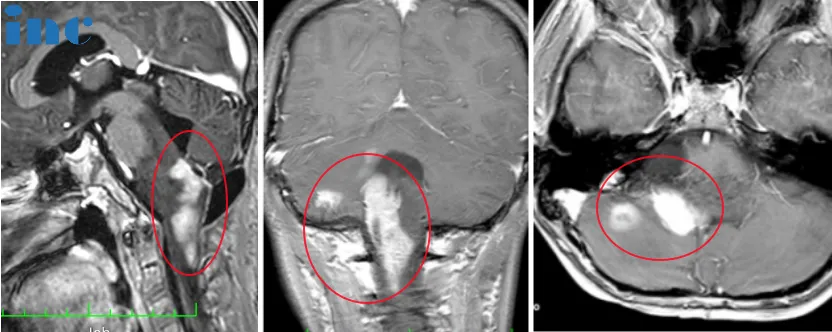

然然术前术后影像对比